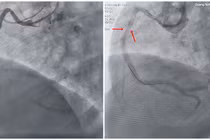

Nhồi máu cơ tim cấp là tình trạng nguy hiểm, có tỷ lệ tử vong cao, đặc biệt khi có biến chứng sốc tim, rối loạn nhịp, ngừng tuần hoàn nguy kịch.

Nhờ kích hoạt quy trình “báo động đỏ” liên viện và nội viện, với tinh thần khẩn trương, đồng bộ cùng sự kiên trì, nỗ lực cấp cứu không ngừng của đội ngũ bác sĩ Bệnh viện Đa khoa tỉnh Quảng Ninh, một nam bệnh nhân 41 tuổi bị nhồi máu cơ tim cấp biến chứng sốc tim, ngừng tuần hoàn nhiều lần do block nhĩ thất hoàn toàn, có những cơn rung thất, được cứu sống kịp thời, vượt qua lằn ranh sinh – tử.